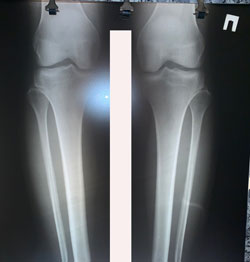

Исходник - 36 лет.

Дата операции - 01.12.2020

Варусная деформация + Ротация с обеих сторон